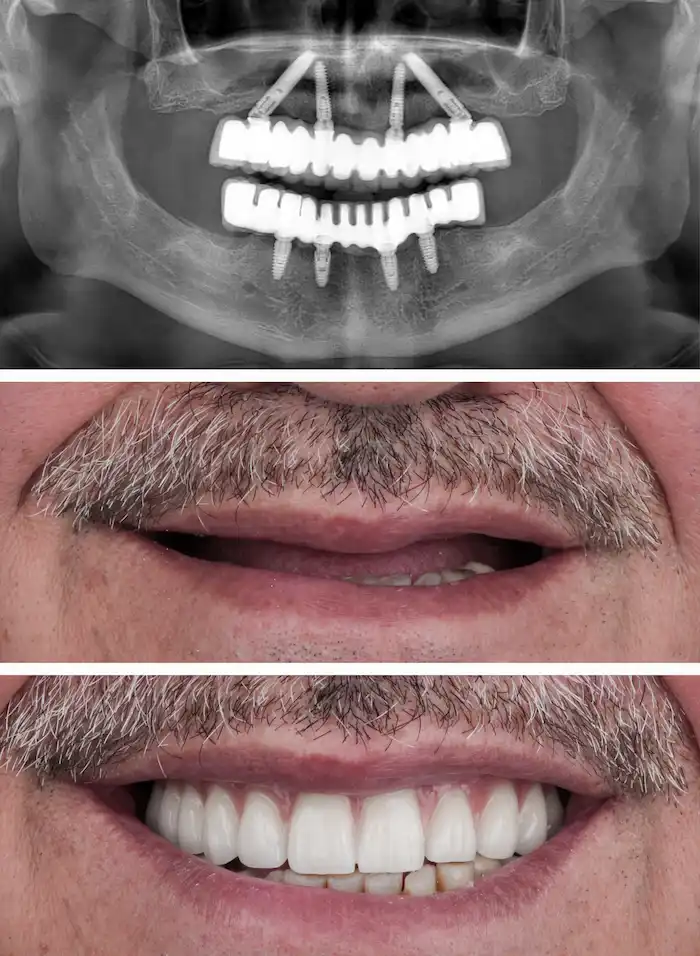

La rehabilitación oral combina distintos tratamientos para restaurar tu boca de forma funcional y estética, permitiéndote volver a comer con normalidad, mejorar tu apariencia y evitar complicaciones a futuro.

Devolvemos la función masticatoria y la armonía de la sonrisa con prótesis, coronas o carillas diseñadas digitalmente para cada paciente.

La rehabilitación oral en Miraflores permite evaluar de forma integral el estado de la boca para restaurar la función al masticar, mejorar la estética dental y devolver equilibrio a toda la estructura oral. A través de un diagnóstico especializado, es posible identificar restauraciones antiguas, coronas deterioradas, implantes con problemas funcionales o alteraciones en la mordida que pueden corregirse mediante un plan de tratamiento personalizado. El objetivo es recuperar una sonrisa saludable, funcional y armónica a largo plazo.

Con esta información se diseña un plan de tratamiento integral que puede incluir implantes dentales, coronas, prótesis o restauraciones avanzadas, buscando siempre resultados funcionales, naturales y duraderos.